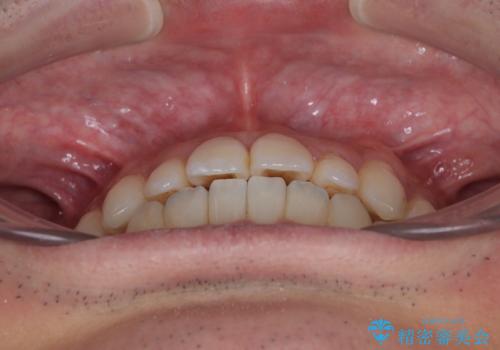

- 前歯のデコボコとクロスバイトを治したいとのことで来院された患者様です。

上下顎ともに歯列全体の側方拡大とIPR(歯と歯の間を削る)によってデコボコとクロスバイトが解消するように設計し、インビザラインにより治療を行うこととしました。

反対咬合特有の治療途中の前歯の干渉が長く続き、治療中に食事をとりにくく、ご迷惑をおかけしました。

前歯の咬み合わせの調整などを行い、安定した咬み合わせに仕上げることができました。